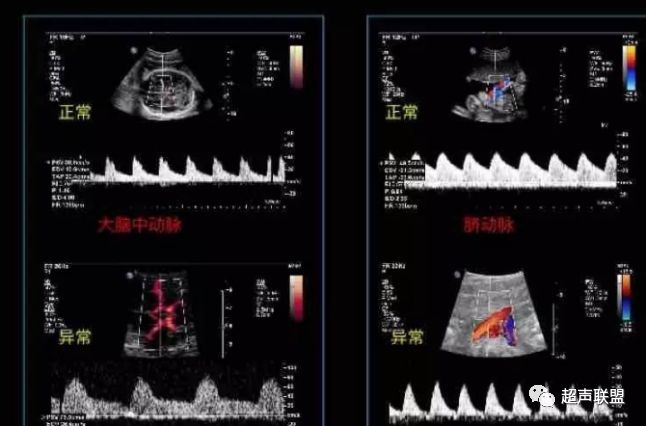

图2 脐动脉舒张期血流消失或反向

图3 正常大脑中动脉血流频谱

图4 大脑中动脉血流阻力减低